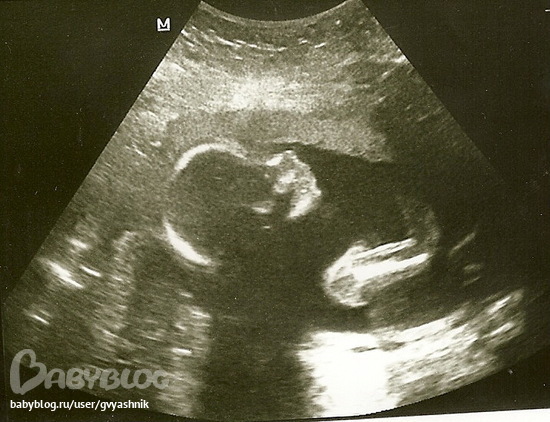

20 недель

Мальчик)